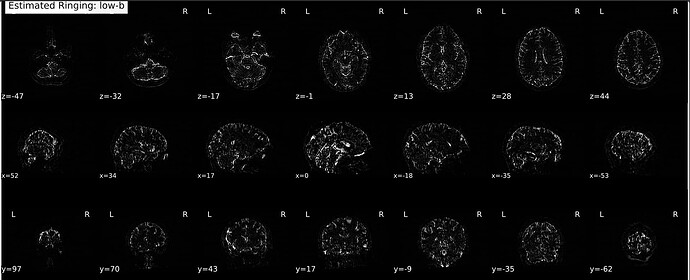

I’ve been processing data for a few different studies using a couple different DSI sequences, two with a multiband Q4 sampling scheme and one multiband cs-DSI—both of which I know @mattcieslak is familiar with (sorry to bother you, Matt). We’ve been noticing that the Gibbs-unringing step in every subject produces some curious outputs: namely, the estimated Gibbs artifacts only appear on the front half of the brain—and I really do mean that literally, insofar as there is a sharp cutoff right at the midpoint of the brain along the phase-encoding axis (see images below).

They are both partial Fourier acquisitions (7/8, so using RPG) with P >> A phase-encoding, so I can rationalize to myself why this could be the case from an acquisition perspective, but given how sharp the transition is, I just want to make sure people smarter than me see this as expected behavior. Will emphasize again this happens in every subject, so as far as I can tell it’s not a random issue arising from head motion or other data quality issues.

An exemplar below (but again, happens for everyone):